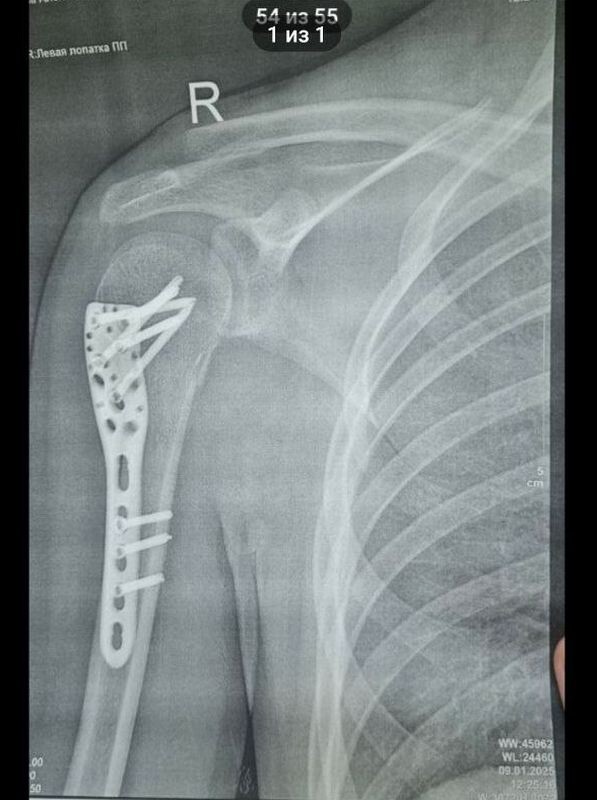

Парень получил перелом трубчатой кости плеча (хирургической шейки плеча), перелом отростка позвоночника: кроме того, пока точно не установлен диагноз после травмы ноги - или разрыв мениска, или хрящевой перелом левого коленного сустава. Парень пережил две операции. Одна, как рассказала корреспонденту портала «маленькая Сызрань» бабушка студента, прошла неудачно; при второй пареньку поставили в плечо пластину, к которой закрепили раздробленную мышцу и то, что осталось от сухожилий (на фото внизу).